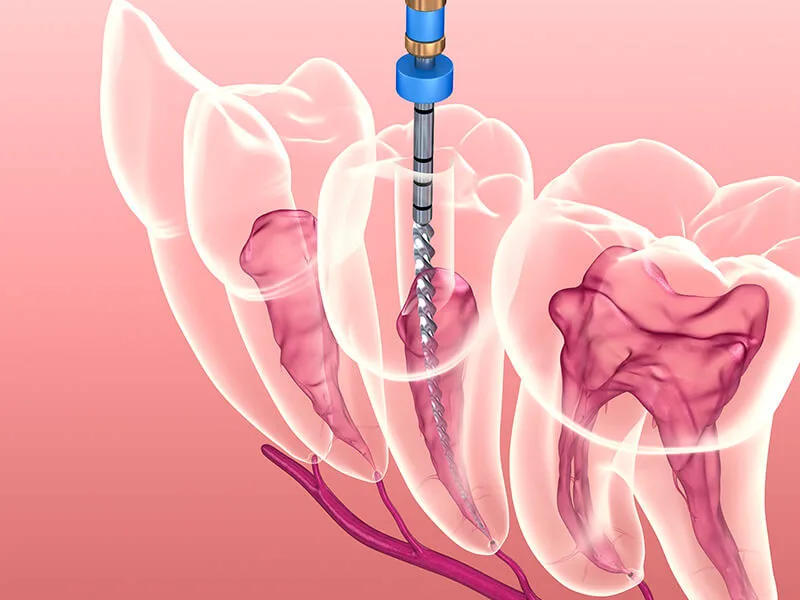

Tecnologias Avançadas: Uso de instrumentação rotatória e localizadores apicais para maior eficácia;

A infraestrutura disponível na capital permite que o procedimento seja nítidamente mais rápido e confortável. O uso de microscopia e materiais de alta fidelidade assegura uma desinfecção profunda e duradoura da região.

Durante o procedimento, o dentista realiza a anestesia da área para remover a polpa inflamada e limpar os canais radiculares.